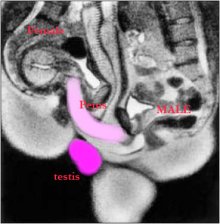

Dr. Pek Van Andel 2000-ben kapott megosztott Ig Nobel-díjat "A férfi és a női nemi szervek tomográfos vizsgálata a közösülés ideje alatt" című munkájáért. (gy.k.: MRI felvétel dugás közben)

13729 4 19 Izé